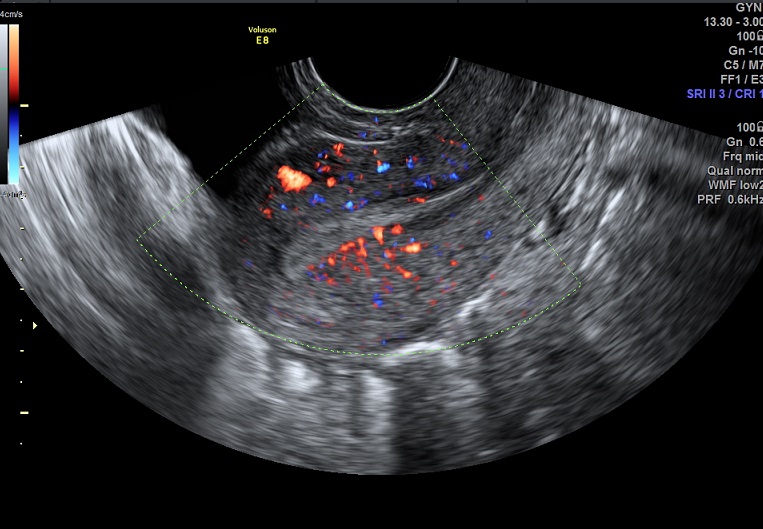

2015-2-17 月经第23天检查 黄体期 |

2015-2-17图示